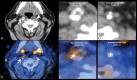

Identification of carotid artery atherosclerosis is conventionally based on measurements of luminal stenosis and surface irregularities using in vivo imaging techniques including sonography, CT and MR angiography, and digital subtraction angiography. However, histopathologic studies demonstrate considerable differences between plaques with identical degrees of stenosis and indicate that certain plaque features are associated with increased risk for ischemic events. The ability to look beyond the lumen using highly developed vessel wall imaging methods to identify plaque vulnerable to disruption has prompted an active debate as to whether a paradigm shift is needed to move away from relying on measurements of luminal stenosis for gauging the risk of ischemic injury. Further evaluation in randomized clinical trials will help to better define the exact role of plaque imaging in clinical decision-making. However, current carotid vessel wall imaging techniques can be informative. The goal of this article is to present the perspective of the ASNR Vessel Wall Imaging Study Group as it relates to the current status of arterial wall imaging in carotid artery disease.